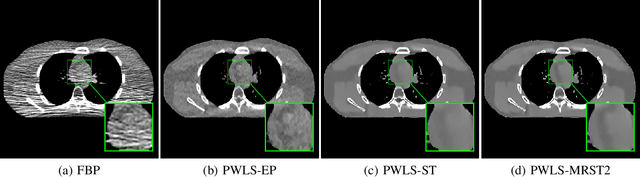

Abstract:Signal models based on sparsity, low-rank and other properties have been exploited for image reconstruction from limited and corrupted data in medical imaging and other computational imaging applications. In particular, sparsifying transform models have shown promise in various applications, and offer numerous advantages such as efficiencies in sparse coding and learning. This work investigates pre-learning a multi-layer extension of the transform model for image reconstruction, wherein the transform domain or filtering residuals of the image are further sparsified over the layers. The residuals from multiple layers are jointly minimized during learning, and in the regularizer for reconstruction. The proposed block coordinate descent optimization algorithms involve highly efficient updates. Preliminary numerical experiments demonstrate the usefulness of a two-layer model over the previous related schemes for CT image reconstruction from low-dose measurements.